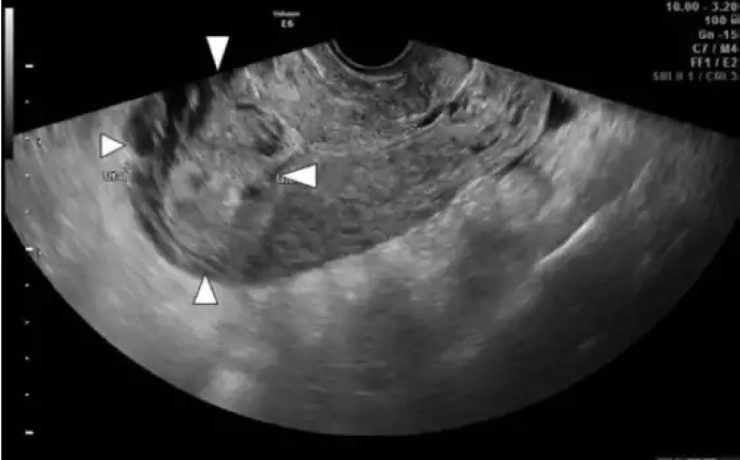

Signo radiológico: “el lirio caído”

El signo del lirio caído , fue descrito hace más de 40 años en pielografía de eliminación y corresponde al aspecto que adquiere el sistema pieloureteral inferior en un riñón con doble sistema excretor, dado por una pelvis renal de orientación horizontal y cálices que se dirigen discretamente hacia cauda.